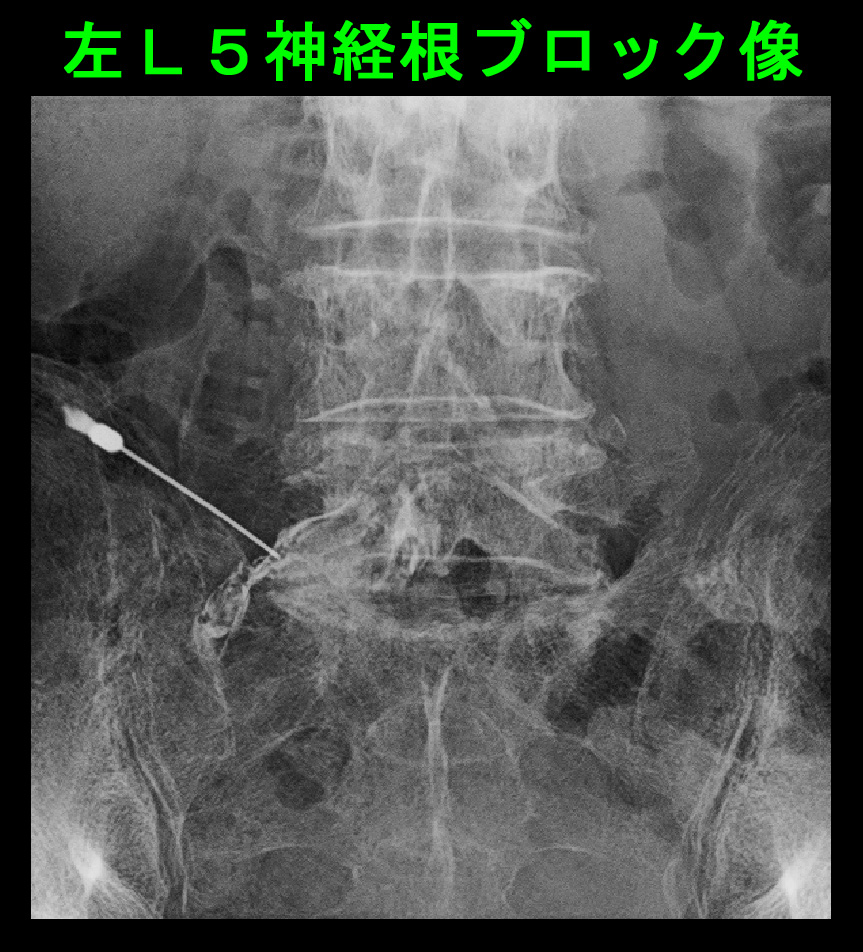

腰椎MRI検査ではL45で重度の脊髄の圧迫(赤矢印)が確認されます。第12胸椎圧迫骨折に起因するオレンジ丸領域の腰痛が軽減して、元々あった腰椎の老化による脊髄圧迫による腰痛と右足指の坐骨神経痛が症状を出したのだと判断します。そこでL45高位で足指の痛みある左側の神経根ブロックを施行しました。

82才男 Xp3.jpg

2週後の5月1日に再診されたときにVAS6の腰痛は0に、VAS4の左足指の痛みも0に軽減していました。左第1足指の指先の針を刺すような痛みは腰に起因する坐骨神経痛であったで間違いないと思います。